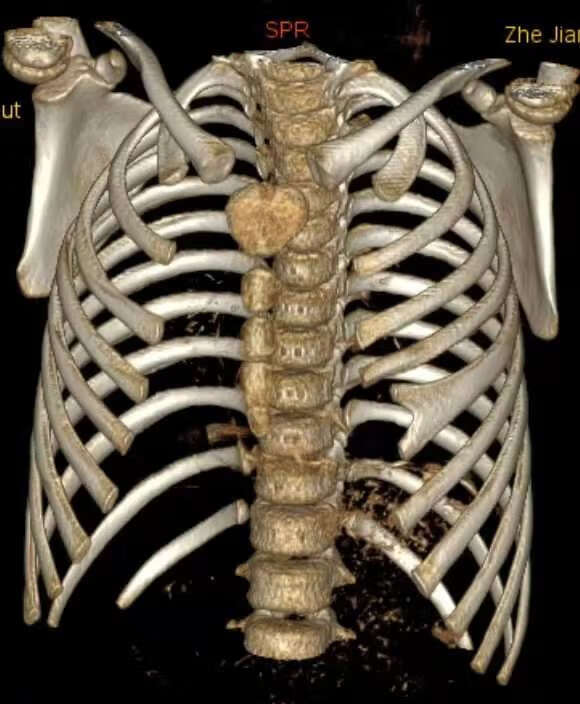

图2CT胸壁重建显示左侧第5硬肋分叉